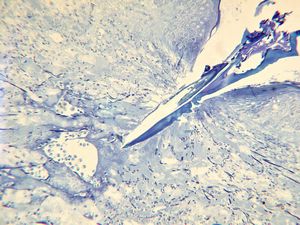

M, 57y. | dermal mycotic lesion … toluidine-blue stained semithin section